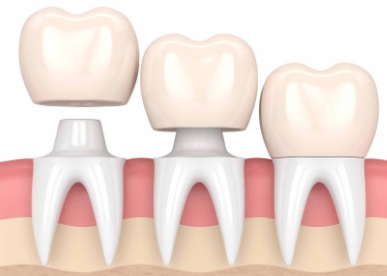

Når skaden på en tann er så stor at restaurering med fyllingsmateriale ikke vil gi tilstrekkelig styrke eller estetikk, må tannen ha en krone. Det slipes da vekk tannsubstans for å gi plass til en ny kappe på tannen som fremstilles av en tanntekniker. Denne limes på den gjenværende tannsubstansen.